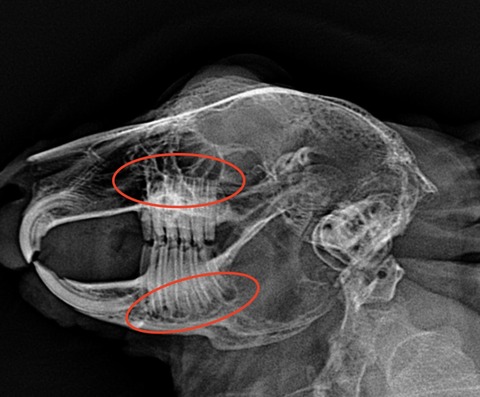

では歯並びが歪んでるとはどういうことかを、レントゲン画像でご紹介します

⇩これが不揃いの子だと

歯根が揃ってないのがわかるかと思います、こういう歯根の子では現状問題なくても膿瘍の発生が警戒されます

健康診断時には歯のレントゲンを撮ってもらっても良いのかもしれませんね

横向けにウサギを寝かせて上からX線を照射し撮影しているので、左右の歯が重なってしまい完璧な評価ができる訳ではないですが、参考にはなります

(理想的にはCTで全ての歯根をチェックするのが望ましい)

歯根の炎症が慢性化すると、歯も変性して濃い白で写ってくるようになります